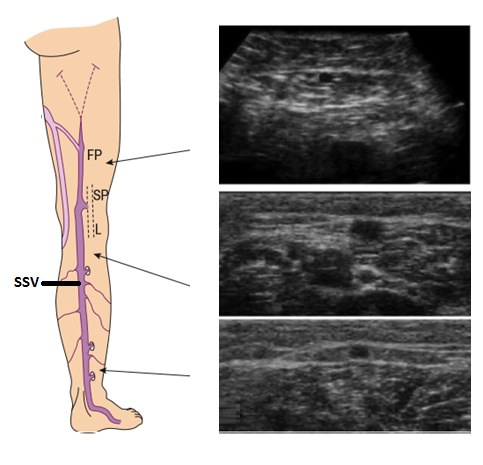

Dublex ultrasonlar, venöz hastalıkların tanı ve tedavisinde kullanılır. Tedavi öncesi ve sonrasında damar yapısının haritasını çıkarmak (haritalandırma), tedavinin takibi açısından büyük önem taşır.